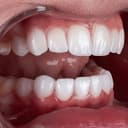

Photography (عکاسی داخل دهان)